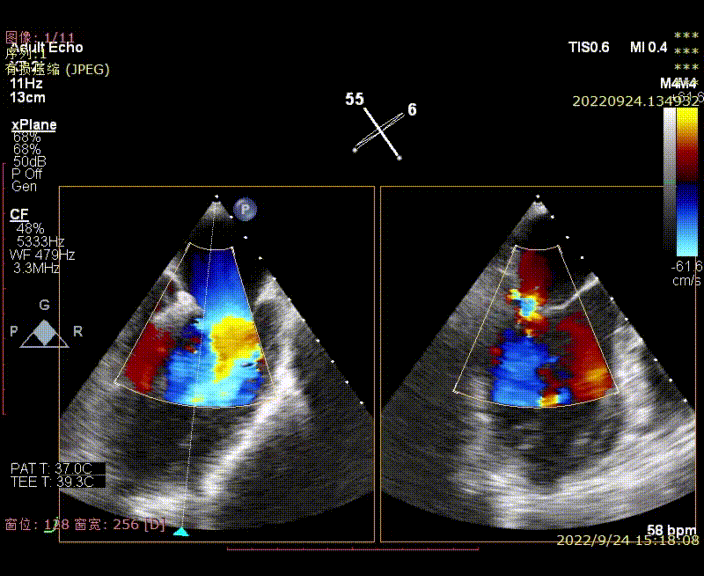

图1-2,术前心超显示大量偏心性二尖瓣反流(反流位置位于P3近PC位置)

图3,由于患者反流位置位于3区偏交界,在MultiVue模式指导下进行操作

图4,夹子植入后消除P3区反流,残余P3偏P2区反流

图5-7,第二夹子植入后,反流降至轻微,术后平均跨瓣压差3mmHg